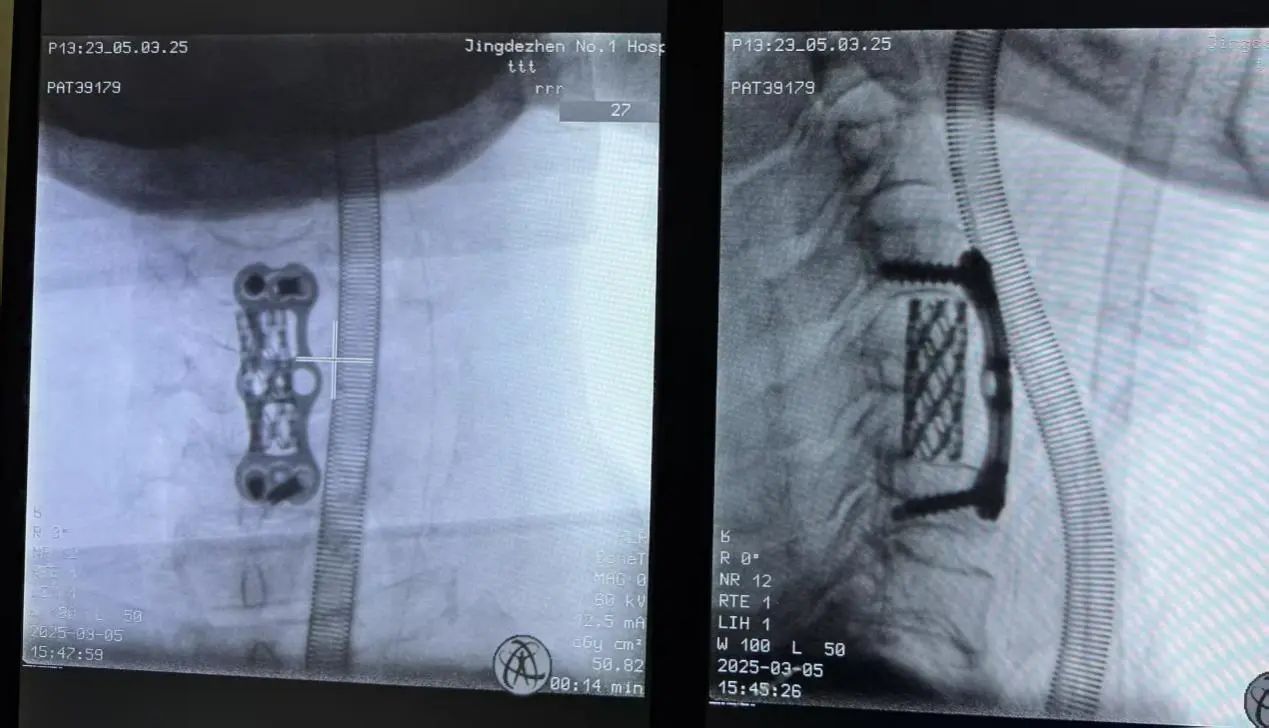

临床上颈椎骨折患者病情轻重不一,有人甚至当场死亡,市一院创伤中心当班的熊军委主诊医师团队在详细了解病情后,立即将患者收入创伤中心重症病房(TICU),并当机立断实施颅骨牵引、脱水、营养神经等一系列关键治疗措施,稳定病情,将患者从死亡线上拉回来。 颅骨牵引常作为颈椎损伤非手术治疗的重要方法,适用于颈椎骨折和脱位患者,尤其是骨折、脱位伴有脊髓损伤者,存在不小的操作难度。一方面,颅骨解剖结构复杂,进针时必须精准掌握部位与深度,稍有差池就可能损伤硬脑膜、血管和神经等重要结构;另一方面,牵引装置安装的精准度要求极高,牵引弓位置、牵引绳方向和张力都要恰到好处,否则会导致颈椎二次损伤等不良后果。此外,颅骨牵引还面临着穿刺部位感染、出血,以及牵引中神经损伤、肌肉萎缩等并发症风险,处理这些问题需要术者具备丰富临床经验。 4天后,在医生们密切复查、时刻关注下,沈大爷病情稍有稳定。颅骨牵引的成功开展,为大爷后期手术创造了有力条件。创伤中心迅速联合院内多学科专家,开展综合诊疗会诊讨论(MDT)。专家们反复研讨、严谨评估,考虑到患者高龄、颈椎脱位十分严重,不适合行脊柱内镜、人工椎间盘等手术,决定由名医工作室专家吕志华主刀,为沈大爷施行颈椎前路减压融合内固定术的开放型手术。 颈椎手术作为脊柱骨科难度系数最高的手术之一,需要对颈部脊髓充分减压,手术操作难度系数大、技术及经验要求高,而颈椎前路手术因靠近气管,需要手术区域完全止血,即使一个小血管渗血都有可能导致颈部血肿压迫气管而危及生命。 吕志华凭借精湛的医术和丰富的经验,精准操作每一个步骤,直接解除脊髓前方的压迫,同时通过植入融合器及内固定装置,恢复颈椎的稳定性。手术历时2小时30分钟,成功完成。 在市一院创伤中心医护人员夜以继日的精心治疗与无微不至的悉心照料下,沈大爷四肢麻木及活动受限明显好转,在颈托保护下逐步可以下床活动。创伤中心骨科组医师最终帮助这位患者成功战胜了这场严重创伤,重新站起来了! 创伤中心负责人施剑明提醒广大市民朋友,在日常生活中要注意保护颈椎,一旦出现颈部疼痛、活动受限、四肢无力等症状,应引起重视。当发生颈部损伤并有颈部以下感觉、运动障碍时,请及时送医并注意谨慎搬运患者,避免严重后果的发生。